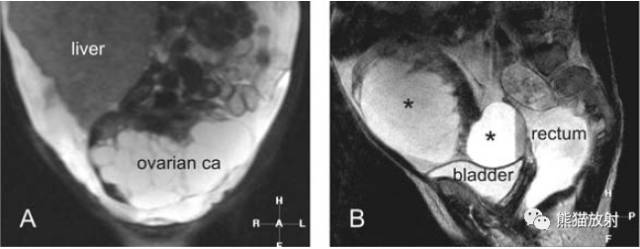

同一例:盆腔卵巢癌MRI表现

A、冠状T2WI:肝脏增大,卵巢癌呈囊实性成分;

B、冠状T2WI:卵巢癌包含多个囊实性肿物(星号);

C.D、轴位T2WI及增强:增厚的囊壁呈相对等或较低信号,增强明显强化。